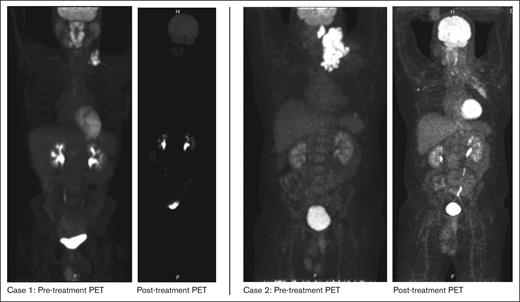

A male aged 46 years with hypertension and obstructive sleep apnea presented with 2-months of an enlarging left neck mass. He had no constitutional symptoms at the time. CT neck and chest were notable for enlarged left cervical and supraclavicular (SCV) LN with maximum diameter of 10.7 cm. Core biopsy of left cervical LN revealed ALK+ LBCL with IHC positive for ALK (granular cytoplasmic pattern), CD45, CD138, weak PAX5, and weak CD30; and IHC negative for CD20, CD3, CD5, CD8, S100, and MCK. PET/CT revealed an FDG-avid conglomerate left neck mass extending into the upper mediastinum and SCV region (SUV max 29) along with a left parapharyngeal lesion. He was, therefore, diagnosed with ALK+ LBCL, stage II, bulky disease. The patient received 1 cycle of CHOP. Within 15 days, he noticed worsening left neck swelling that was confirmed as clinical progression. Despite a dexamethasone burst (40mg daily for 4 days), he had no symptomatic relief and was urgently treated with radiation to the left neck mass (50 Gy/ 20 fractions). Within a few days after the completion of radiation therapy, he noticed a new left axillary LN. CT imaging confirmed enlarged bilateral axillary lymphadenopathy with reduction in left SCV LN. For systemic relapse, we were able to get approval for crizotinib 250mg twice daily, which he began approximately 1 month after radiation completion. The patient noted a drastic improvement in axillary lymphadenopathy within days. Upon initiation of crizotinib, there was a transient rise in liver function tests (AST 151 U/L, ALT 323 U/L) that resolved with hydration and conservative management. PET/CT completed approximately 8 weeks after radiation therapy noted a PR. However, about 2 months after crizotinib use, he reported enlarging bilateral axillary lymphadenopathy. PET/CT at this time confirmed interval PD in bilateral axilla along with a new left pleural effusion and minimally FDG-avid pulmonary nodules. He was referred back to radiation oncology and began localized radiation to the left axilla (50 Gy/ 20 fractions) and was switched to alectinib 600mg twice daily around the same time. Post-treatment PET/CT has revealed resolution of left axillary LN, ongoing reduction in left cervical LN, and mixed response within right axillary LN. He maintained PR on alectinib for 6 months but subsequently developed relapsed disease predominantly in the right axilla and right SCV nodes. Right axillary biopsy confirmed ALK+ LBCL with immunohistochemical stains negative for CD30 and CD19. TEMPUS testing from lymph node biopsy was only notable for CLTC-ALK rearrangement and copy number loss of ATM. He began focal radiation to right axilla, and for systemic therapy, was switched to lorlatinib 100 mg daily which he has been on for at least 6 months with evidence of complete metabolic response on PET. His course was otherwise complicated by coronavirus disease 2019 (COVID-19) with incidental findings of a left lower lobe subsegmental PE that was managed with apixaban.

In summary, we report the first case series of adult patients with ALK+ LBCL who were treated with ALK inhibitors and attained meaningful and durable clinical responses. Both our patients had diseases that were resistant to standard-of-care treatment with CHOP. Initiation of an ALK inhibitor led to a rapid clinical response in both patients as demonstrated in Figure 1. Our first patient from case 1 has done exceptionally well with crizotinib as demonstrated by ongoing CR for >6 years without any dose-limiting toxicities. In contrast, our second patient, after an initial response, had PD after 3 months of crizotinib therapy and, thus, was switched to a second-generation ALK inhibitor, alectinib. He tolerated this well with response lasting 6 months and now in a CR while being treated with lorlatinib currently again in a CR after progressing while on alectinib.